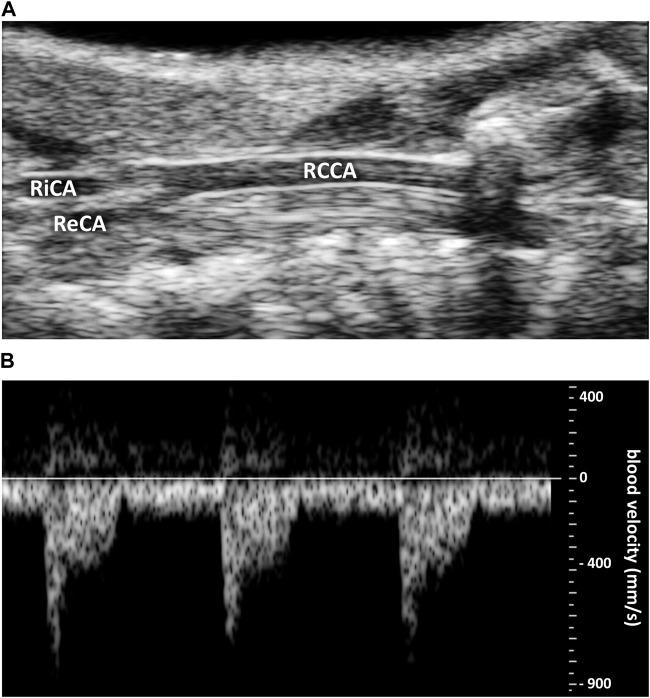

Blood flow produces fluid shear stress (SS), a frictional force parallel to the blood flow, on the endothelial cell (EC) layer of the lumen of the vessels. ECs themselves are sensitive to this frictional force in terms of directionality and intensity. The aim of this study was to determine the physiological shear stress value during the cardiac cycle and EC polarity and orientation from blood flow in healthy male and female mouse carotid artery. Experimentation is done on anesthetized male and female 8-week-old C5BL/6J mice. measurements of maximum blood velocity and vessel diameter in diastole and systole were performed on the right common carotid artery by Doppler ultrasound imaging. Blood viscosity (total and plasmatic) and hematocrit were determined on blood samples. For SS calculation, we developed a new method assuming heterogenous blood flow, i.e., a red cell central plug flow surrounded by a peripheral plasma sheath flow, and computing SS from vessel diameter and hemodynamical measurements (maximal blood velocity, hematocrit and plasmatic viscosity). Results were compared with the classical method assuming a homogenous blood flow with constant apparent total blood viscosity. EC polarity and orientation were determined on the carotid endothelium by confocal imaging after labeling of the EC nucleus and Golgi apparatus. Diastolic and systolic SS were 6 ± 2.5 Pa and 30 ± 6.5 Pa, respectively. Total blood and plasmatic viscosity was 4 ± 0.5 cP and 1.27 cP, respectively. ECs were polarized and significantly oriented against blood flow. No sex difference was identified.

血流会在血管腔的内皮细胞(EC)层上产生流体剪切应力(SS),这是一种与血流平行的摩擦力。内皮细胞本身在方向性和强度方面对这种摩擦力很敏感。本研究的目的是确定健康雄性和雌性小鼠颈动脉在心动周期中的生理剪切应力值以及内皮细胞的极性和取向与血流的关系。实验在8周龄麻醉的雄性和雌性C5BL/6J小鼠身上进行。通过多普勒超声成像对右侧颈总动脉在舒张期和收缩期的最大血流速度和血管直径进行测量。对血样测定血液粘度(全血和血浆)和血细胞比容。为了计算剪切应力,我们开发了一种新方法,假设血流不均匀,即红细胞在中央形成栓塞流,周围是外周血浆鞘流,并根据血管直径和血液动力学测量值(最大血流速度、血细胞比容和血浆粘度)计算剪切应力。将结果与假设血流均匀且表观全血粘度恒定的经典方法进行比较。在内皮细胞核和高尔基体标记后,通过共聚焦成像确定颈动脉内皮细胞的极性和取向。舒张期和收缩期的剪切应力分别为6±2.5帕和3±6.5帕。全血和血浆粘度分别为4±0.5厘泊和1.27厘泊。内皮细胞呈极化状态,且明显与血流方向相反排列。未发现性别差异。